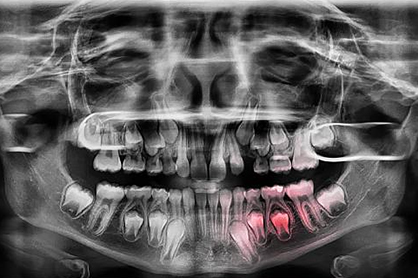

Severe Bone Loss